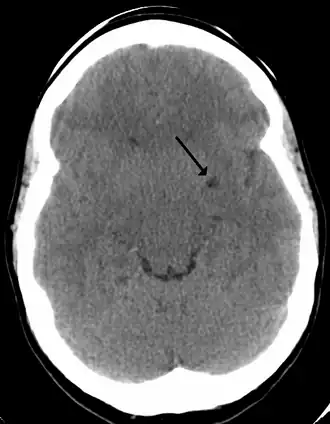

A perivascular space, also known as a Virchow–Robin space, is a fluid-filled space surrounding certain blood vessels in several organs, including the brain,[1] potentially having an immunological function, but more broadly a dispersive role for neural and blood-derived messengers.[2] The brain pia mater is reflected from the surface of the brain onto the surface of blood vessels in the subarachnoid space. In the brain, perivascular cuffs are regions of leukocyte aggregation in the perivascular spaces, usually found in patients with viral encephalitis.

In humans, perivascular spaces surround arteries and veins can usually be seen as areas of dilatation on MRI images. While many normal brains will show a few dilated spaces, an increase in these spaces may correlate with the incidence of several neurodegenerative diseases, making the spaces a topic of research.[4]

Perivascular spaces are most commonly located in the basal ganglia and white matter of the cerebrum, and along the optic tract.[13] The ideal method used to visualize perivascular spaces is T2-weighted MRI. The MR images of other neurological disorders can be similar to those of the dilated spaces. These disorders are:[7]

Perivascular spaces are distinguished on an MRI by several key features. The spaces appear as distinct round or oval entities with a signal intensity visually equivalent to that of cerebrospinal fluid in the subarachnoid space.[7][14][15] In addition, a perivascular space has no mass effect and is located along the blood vessel around which it forms.[14]

The clinical significance of perivascular spaces comes primarily from their tendency to dilate. The importance of dilation is hypothesized to be based on changes in shape rather than size.[13] Enlarged spaces have been observed most commonly in the basal ganglia, specifically on the lenticulostriate arteries. They have also been observed along the paramedial mesencephalothalamic artery and the substantia nigra in the mesencephalon, the brain region below the insula, the dentate nucleus in the cerebellum, and the corpus callosum, as well as the brain region directly above it, the cingulate gyrus.[5] Upon the clinical application of MRI, it was shown in several studies that perivascular space dilation and lacunar strokes are the most commonly observed histological correlates of signaling abnormalities.[13]